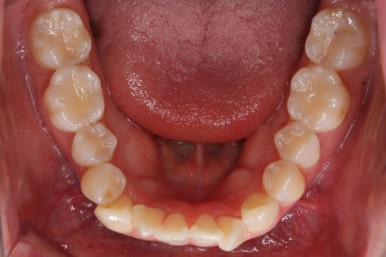

다시 이번 환자분으로 돌아가, 입 안모습을 보시겠습니다.

부산무턱교정 키다리아저씨치과에서 처음 내원하셨을 당시의 입 안의 모습입니다.

아래턱이 작아서 상대적으로 윗니들이 많이 돌출되었고, 뻐드러져 있습니다. 윗니들이 배열되어 있는 형태도 V자에 가깝게 입천장이 좁은 양상입니다.

얼굴모습과 입 안의 모습을 모두 고려하여 발치교정을 하기로 하였습니다.

결국 앞니를 뒤로 집어 넣어야 여러 가지가 해결이 되는데, 앞니를 뒤로 넣으려면 자리가 필요하고, 발치를 선택할 수 밖에 없는 상황이었습니다.

다만, 아랫니까지 뽑기에는 적절치 않아서 윗니만 발치하고 진행하기로 하였습니다.